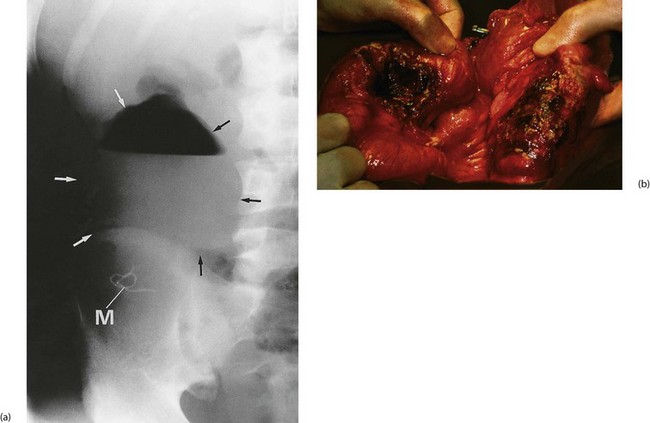

Acute bowel ischaemia is an uncommon postoperative complication, usually occurring after abdominal aortic surgery. Infarction of the sigmoid colon follows inferior mesenteric artery ligation (usually a necessary part of the operation) if the collateral blood supply is compromised by obliterative atherosclerosis of the remaining mesenteric arteries. Fortunately, this is rare. The patient has usually progressed well at first then deteriorates unexpectedly several days after operation, often passing fresh blood per rectum. If untreated at this stage, the patient later collapses with peritonitis due to colonic necrosis and perforation.

Clinical signs of acute bowel ischaemia are non-specific, but often the degree of pain and collapse is out of proportion to the minimal abdominal signs. Plain abdominal X-ray may show ‘thumb printing’ of the affected bowel or the characteristic appearance of gas in the bowel wall. If acute bowel ischaemia is suspected, laparotomy must usually be performed urgently as perforation will soon occur and is nearly always fatal. Even with timely surgery, the prognosis is bleak.